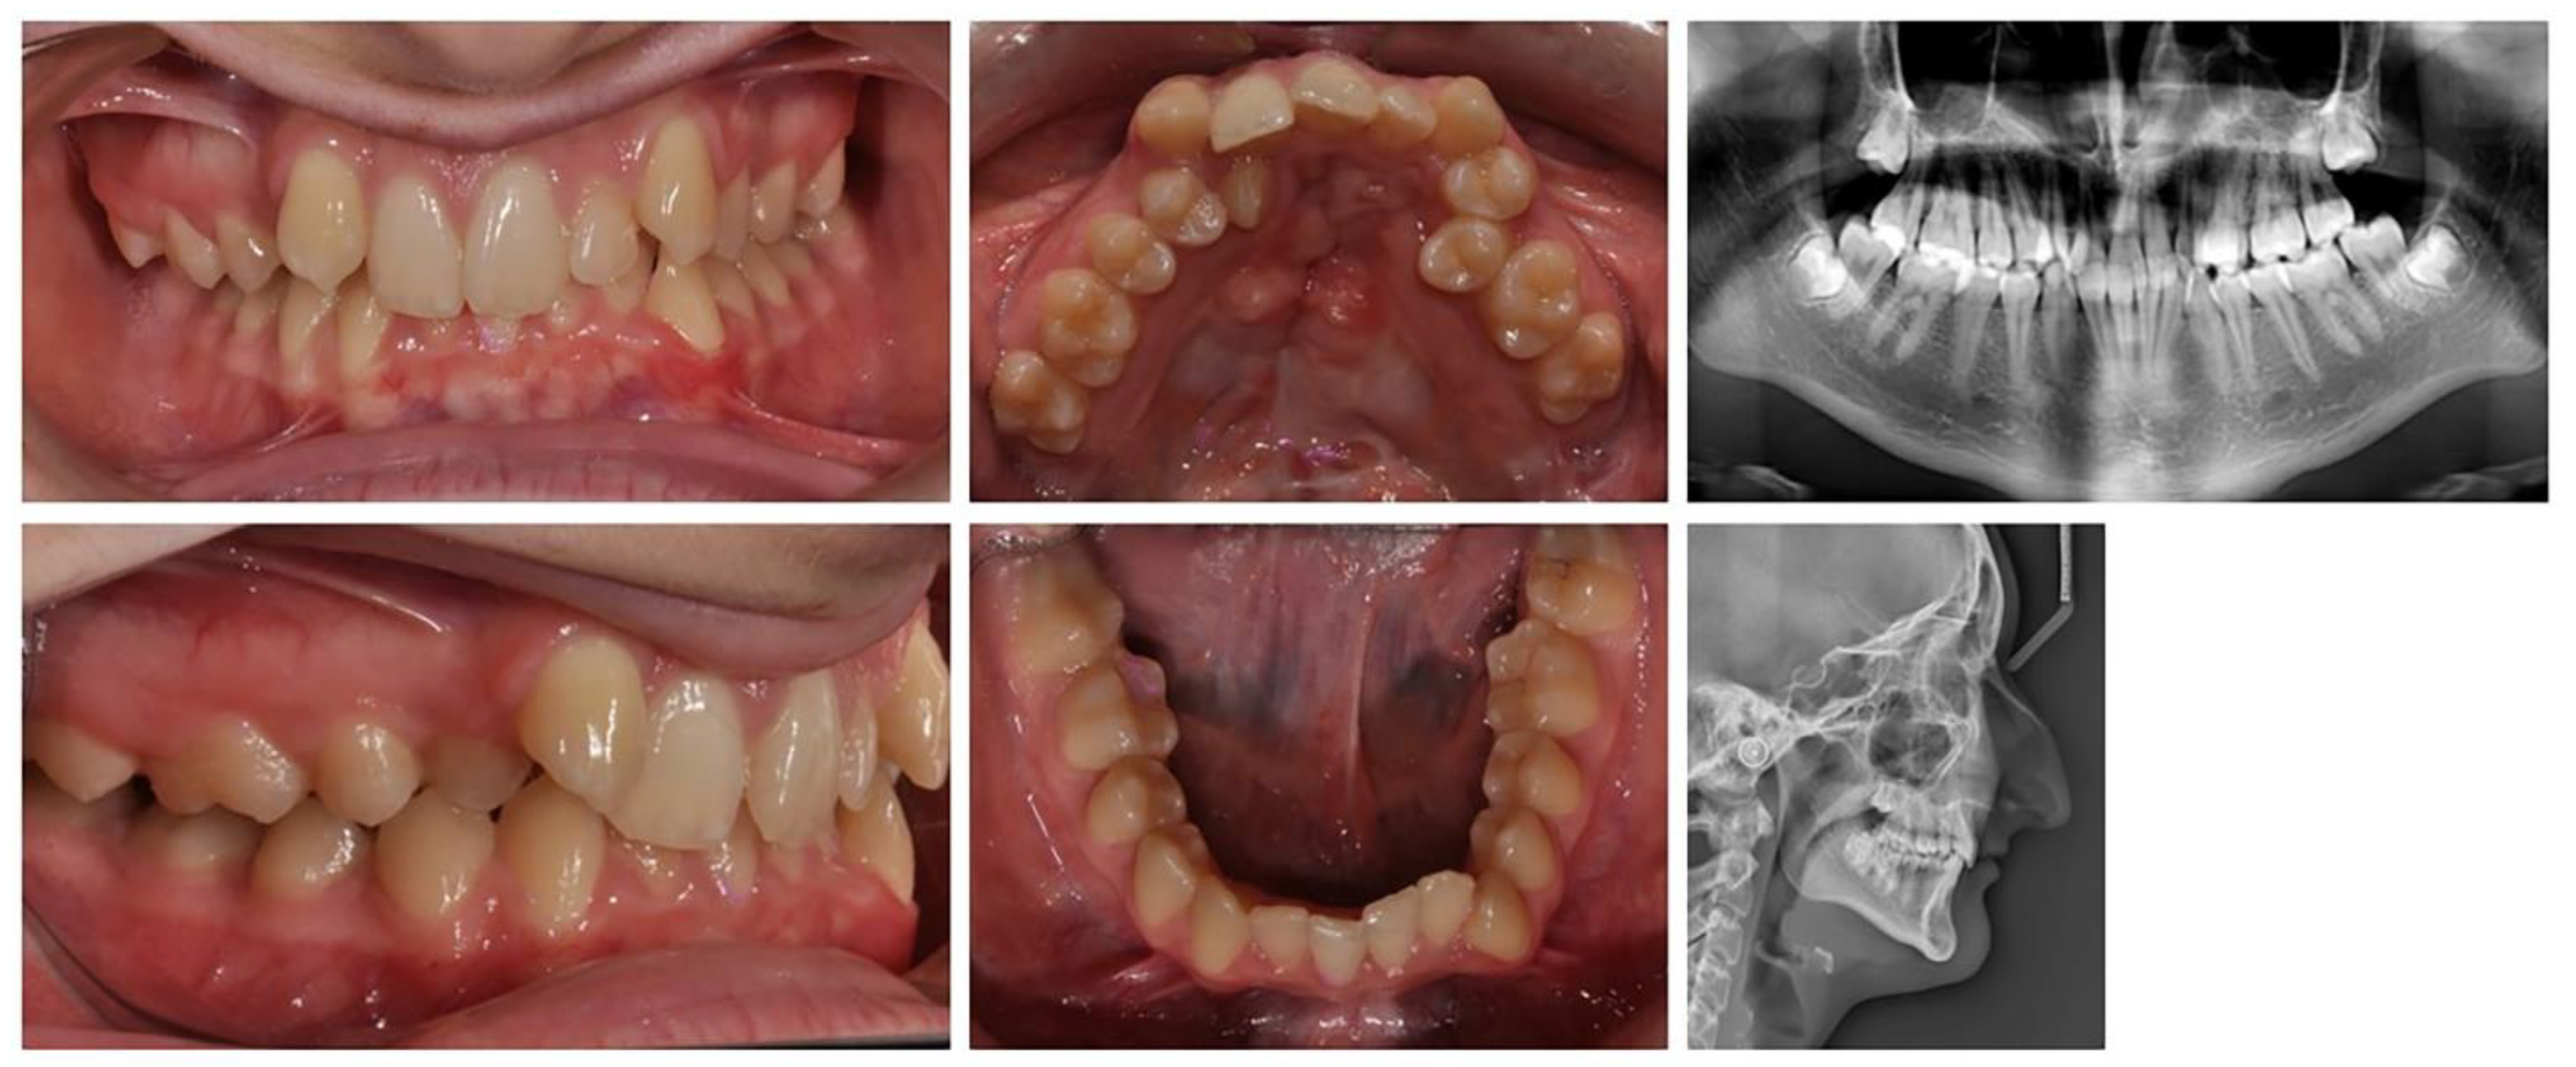

2.2.3. A 17-year-old female patient with a surgically repaired cleft of the hard palate. The patient's complaints are worsened aesthetics. During the first clinical examination, a reduced perimeter of the upper dental arch was found, crowding was observed both in the frontal and in the middle segment (in the area of premolars), the shape of the dental arch was changed - trapezoidal. The upper right lateral is located at the palate and the canine is medially located in contact with the central incisor. The upper frontal teeth are retruded and extruded, the bite is covered (Figure 6).

Figure 6. Initial status of patient with a surgically repaired cleft of the hard palate.